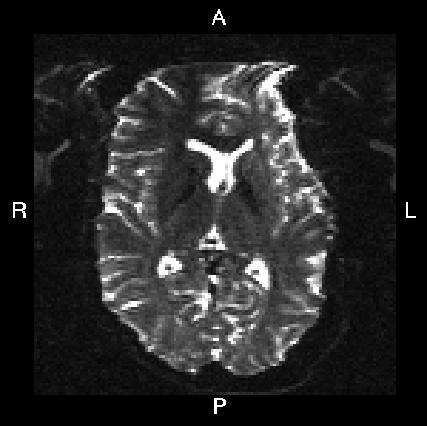

Below you see four examples of images acquired with different phase encoding. Below the images you see what you would find in the PDF protocol generated on a Siemens scanner for these acquisitions. Unfortunately I don't have enough experience of other scanner manufacturers to know where to find the information from those.

If you are uncertain about how to create your own --acqp file I suggest you get your scanner protocol, load your images into FSLVIEW and then find which of the images below that looks most like then one you have. When you have done that compare the "Phase enc." entry below that image with that in your protocol. When you are happy that you have found the right column you can use the three first values from the vector below the image.

| What you see in FSLeyes |

|---|---|---|---|---|

Phase enc. dir R >> L Echo spacing 0.96 ms EPI factor 128 |

| In --acqp file | 0 1 0 0.095 | 0 -1 0 0.095 | 1 0 0 0.122 | -1 0 0 0.122 |